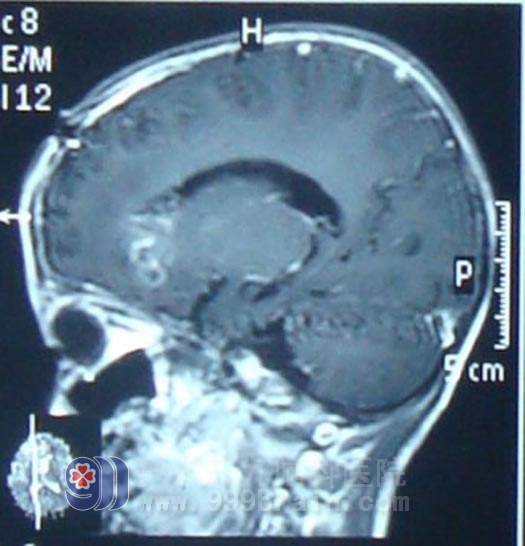

入院后积极完善术前相关检查,于2月11日在广东三九脑科医院神经外科行右额叶及基底节区肿瘤大部分切除术,术后病理示间变型室管膜瘤Ⅲ级。术后行同步放化疗,头部适形放疗完成54Gy,后再行几程辅助化疗后复查头颅MR显示强化及水肿范围明显缩小,康康精神状态良好,未诉不适。http://www.999brain.com/

放疗后